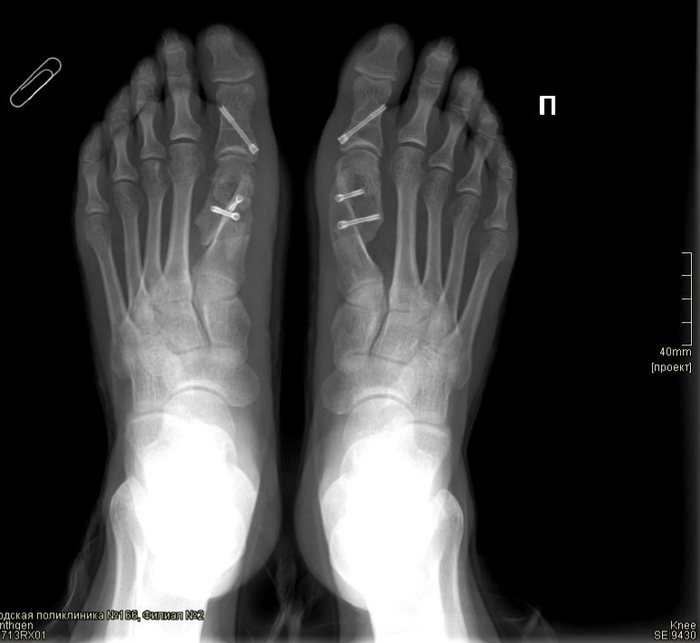

Продолжение поста «Hallux valgus. Вальгусная деформация стопы. Косточка. Личный опыт»

Пара человек просила показать что будет через пол года - год. Показываю что спустя 9 месяцев. Ничего не болит, обувь теперь беру на размер больше, для комфорта. Вернулась на тренировки, скальники конечно не домашние тапки, но уже лучше, и в работу тела активно включилась и стопа.

Что интересно, после операции на стопах (предыдущий пост) мне стало легче контролировать спастику на ноге, и я лучше ею шевелю. Прочувствовала где были лишние спазмы и научилась с ними работать.

Hallux valgus. Вальгусная деформация стопы. Косточка. Личный опыт

Показания к операции имелись на обеих стопах. Сначала хотела сделать одну – по квоте, потом (ориентировочно через полгода – год) вторую, чтобы тоже по квоте. Но прикинув сколько пробуду за оба раза на больничных поняла, что сразу обе (одна по ОСМ, вторая – платно) выгоднее и эмоционально, и физически, и финансово. Своим выбором довольна. Цена за вторую ногу на февраль 2023 в Москве 70т.

Операции были разбиты на два дня. Стопа посложнее 13 февраля, стопа с меньшей деформацией 15 февраля. Проходят под эпидуральной анестезией, и ….вот тут я не совсем поняла, что это, наверно общий наркоз, но на второй операции я проснулась и сказала доктору, что чувствую как ковыряется в моей ноге, он спросил больно ли, я ответила, что нет, и спокойно уснула дальше. Предположу, что на второй операции мне просто меньше дозировку дали, так как после первой отходняк был тяжелый, знобило аж кровать скрипела, после второй было легче.

Отдельной темой костные мозоли и винты. Врач предупредил, что винты постоянные, но если будут натирать обувью, то их достают, после сращения костей. Соответственно, сейчас, спустя 2 месяца глядя на ноги я не могу понять костные мозоли или винты – разберусь позже.